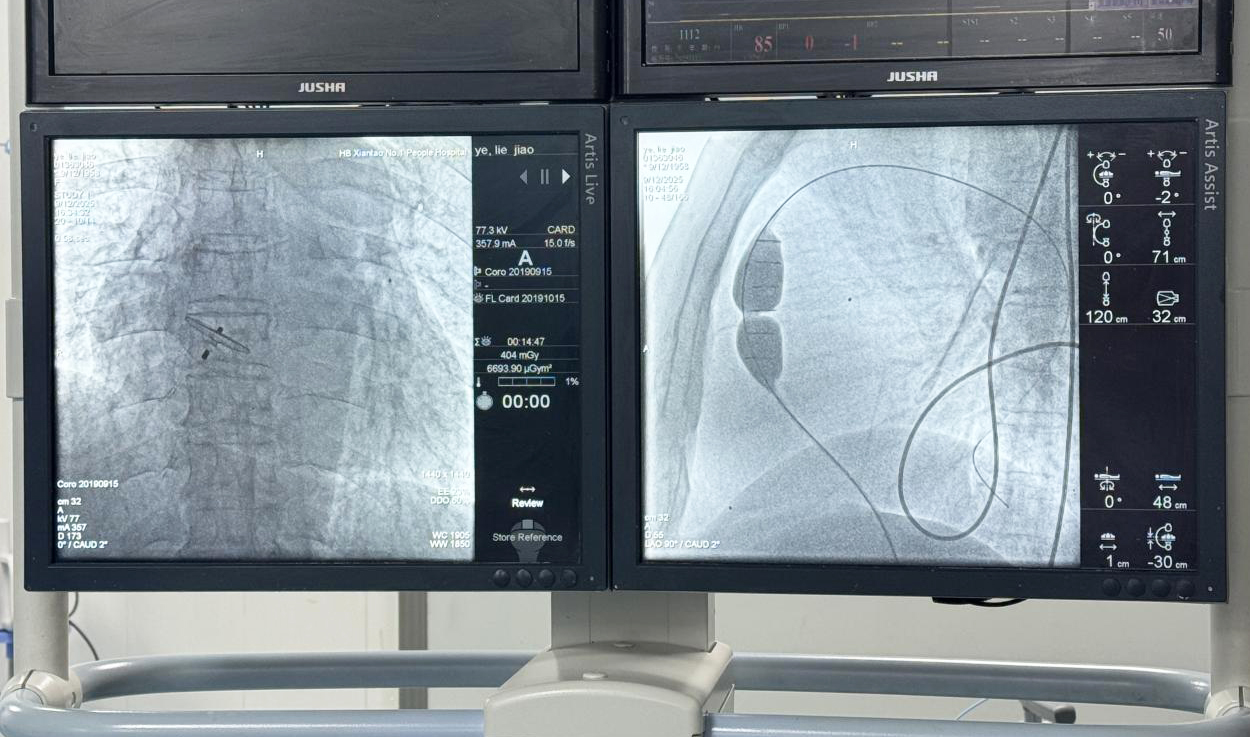

术中,市一医手术团队与省级专家密切配合,在患者大腿根部进行微穿刺,在影像引导下将球囊导管通过血管精准送达狭窄的肺动脉瓣处。充盈球囊后,成功扩张了狭窄的瓣膜,同期完成了卵圆孔未闭的封堵。整个手术无需开胸,创伤极小。术后即刻,患者的血氧饱和度从术前的80%显著提升至100%。

术后第3天,肖奶奶已可下床活动,最直观的改变是口唇颜色由青紫转为红润。监测显示其血氧饱和度稳定在100%,这意味着她全身组织获得了充足的氧气供应。李军主任表示,血氧水平的根本改善将显著提升患者的活动耐力和生活质量,心肺功能也会逐渐改善,更重要的是能避免因长期缺氧导致的器官损伤。